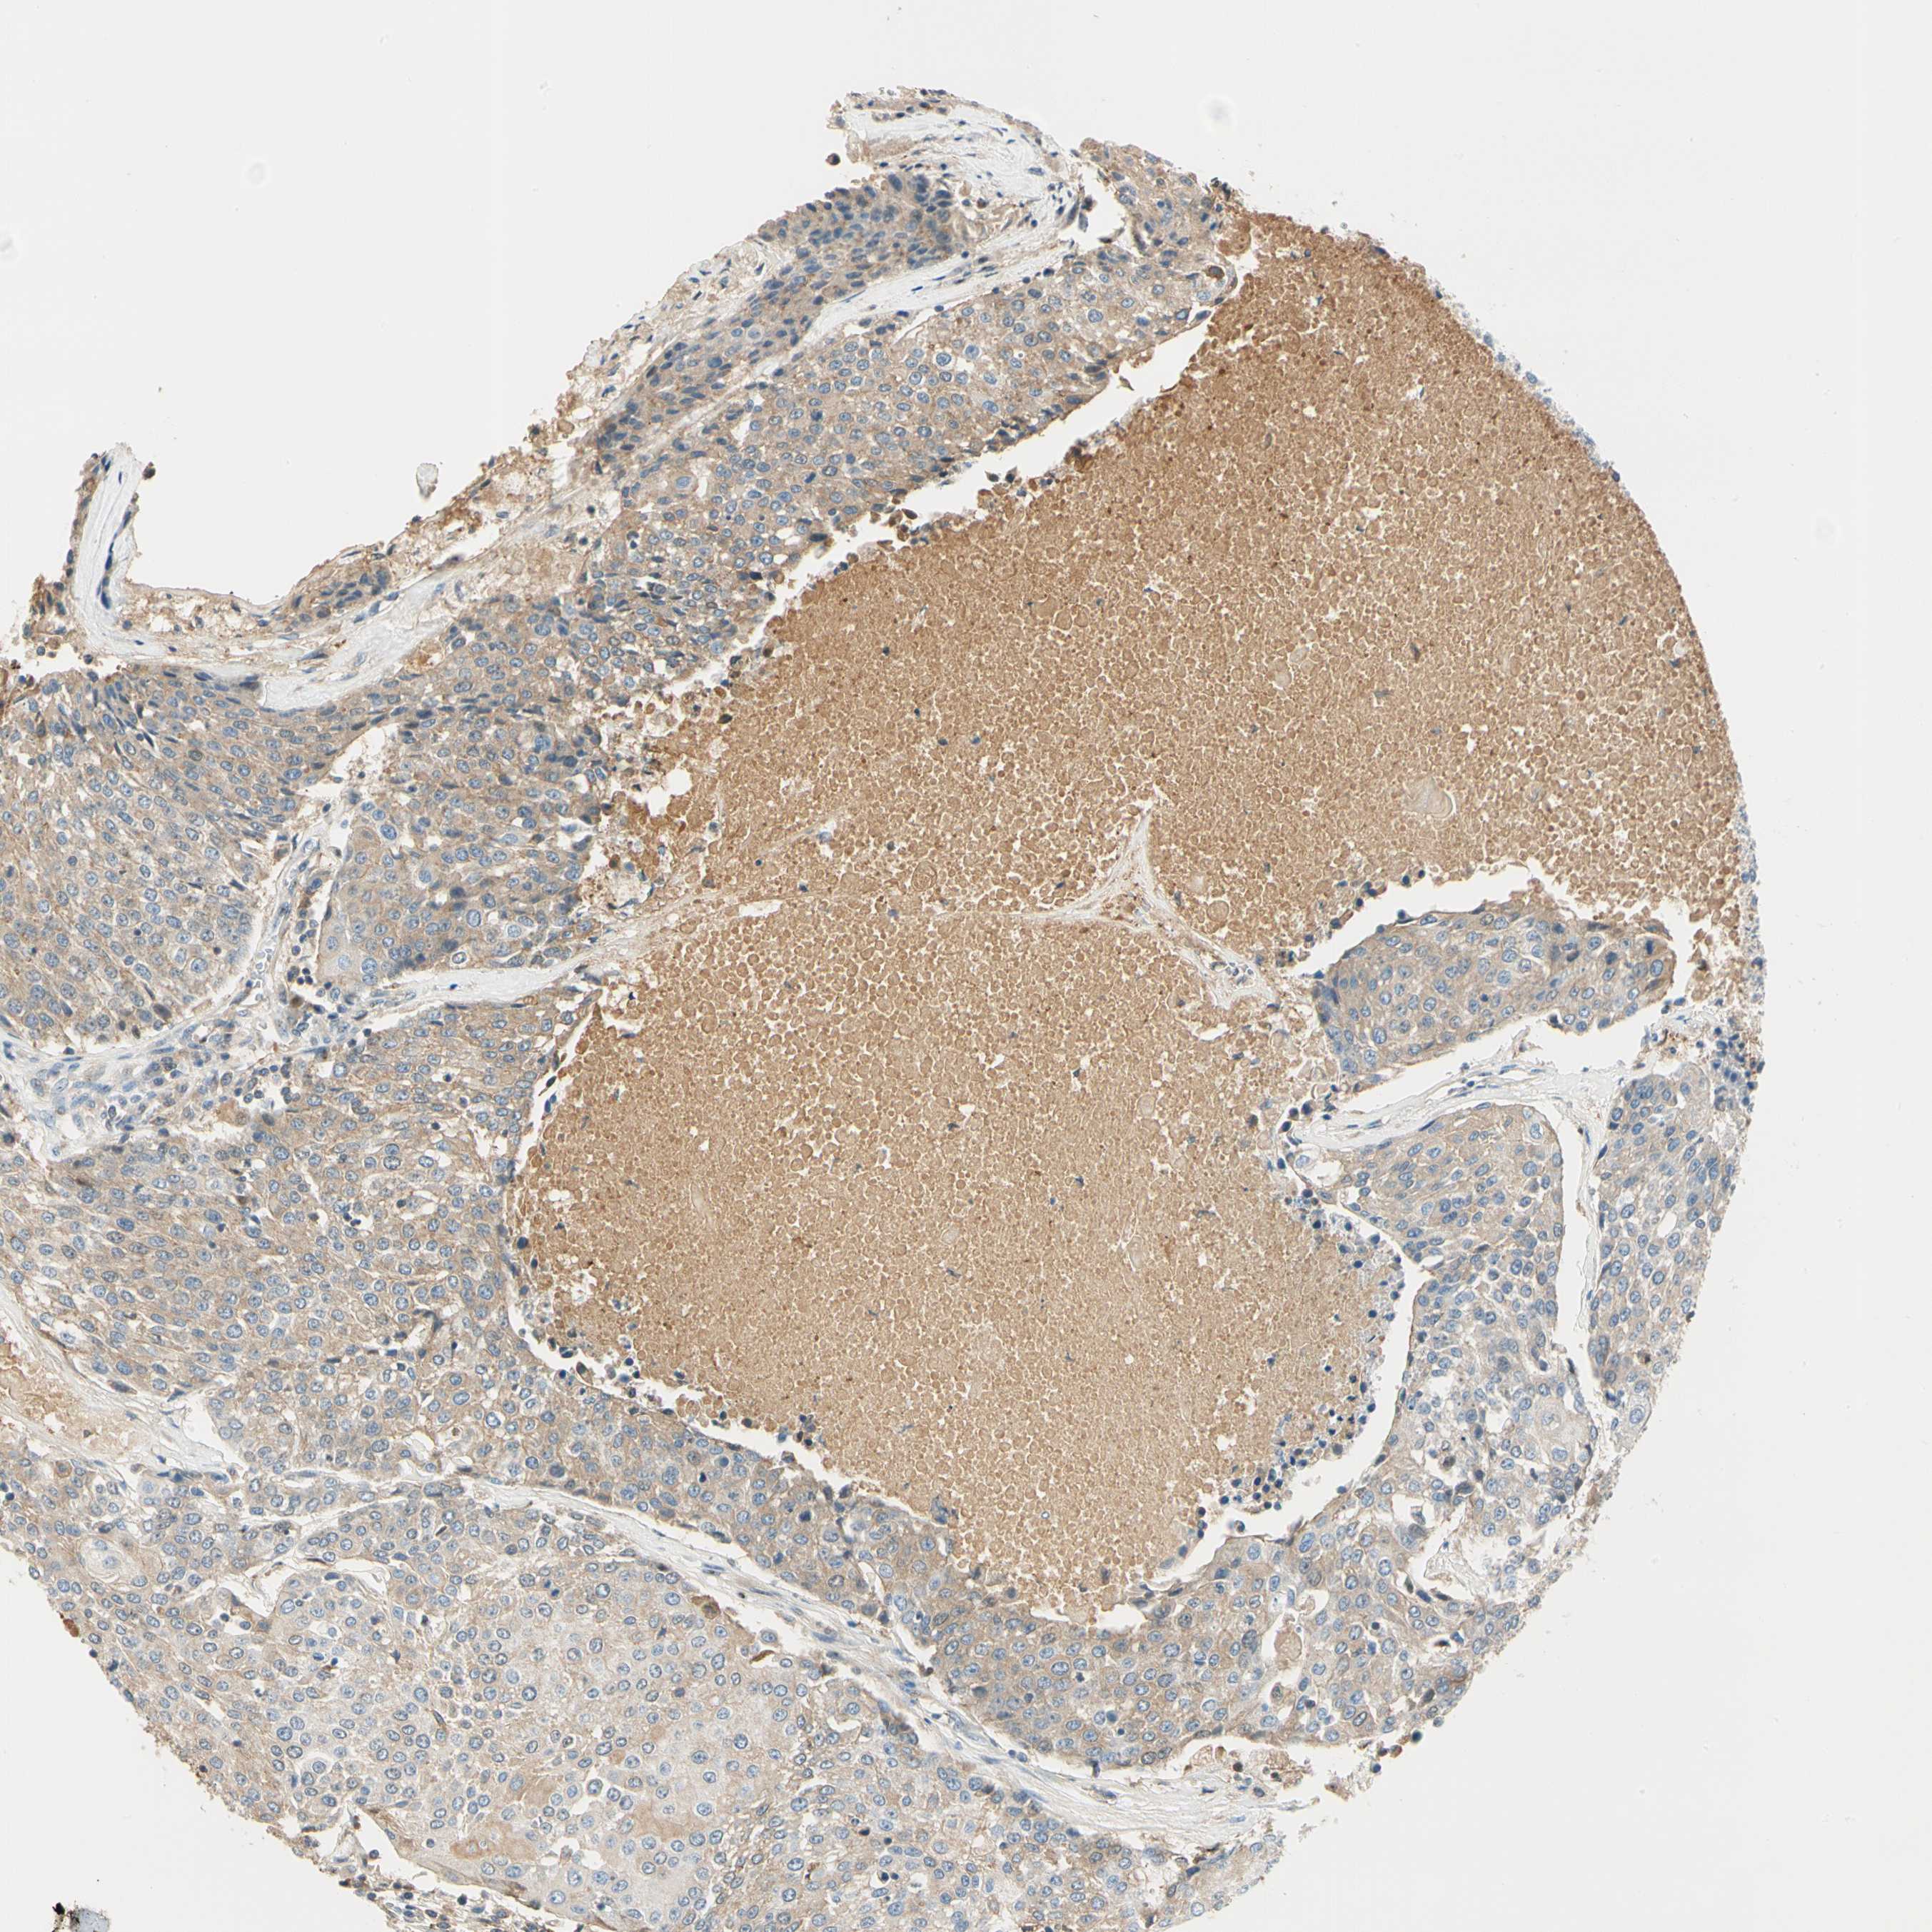

UROTHELIAL CANCER - Protein expressioni

A mouse-over function shows sample information and annotation data. Click on an image to view it in a full screen mode. Samples can be filtered based on level of antibody staining by selecting one or several of the following categories: high, medium, low and not detected. The assay and annotation is described here.

Note that samples used for immunohistochemistry by the Human Protein Atlas do not correspond to samples in the TCGA dataset.

Antibody stainingi

Antibody staining in the annotated cell types in the current human tissue is reported as not detected, low, medium, or high, based on conventional immunohistochemistry profiling in selected tissues. This score is based on the combination of the staining intensity and fraction of stained cells.

Each image is clickable and will lead to virtual microscopy that enables deeper exploration of all samples and also displays staining intensity scores, fraction scores and subcellular localization as well as patient and tissue information for each sample.

Antibody HPA008069

Antibody CAB078183

Staining

High

Medium

Low

Not detected

Intensity

Strong

Moderate

Weak

Negative

Quantity

>75%

75%-25%

<25%

None

Location

Nuclear

Cytoplasmic/membranous

Cytoplasmic/membranous,nuclear

Urothelial carcinoma, Low grade

Urothelial carcinoma, High grade

Urothelial carcinoma, NOS